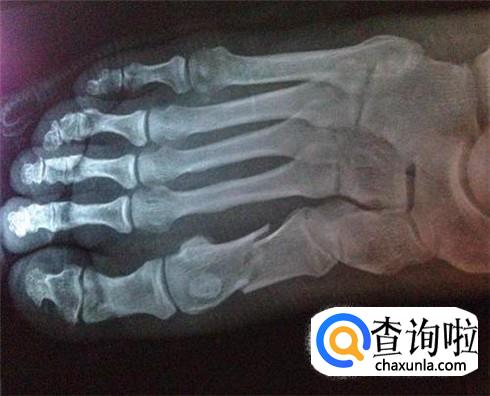

及时检查进行确诊

不要觉得只是轻微的骨裂,没有什么大问题,也不影响自己的行动,所以对此并不以为然,这样是不可以的,一定要先去医院,做一个拍片检查,由医生来给你确诊一下,你骨裂的程度是怎么样的。